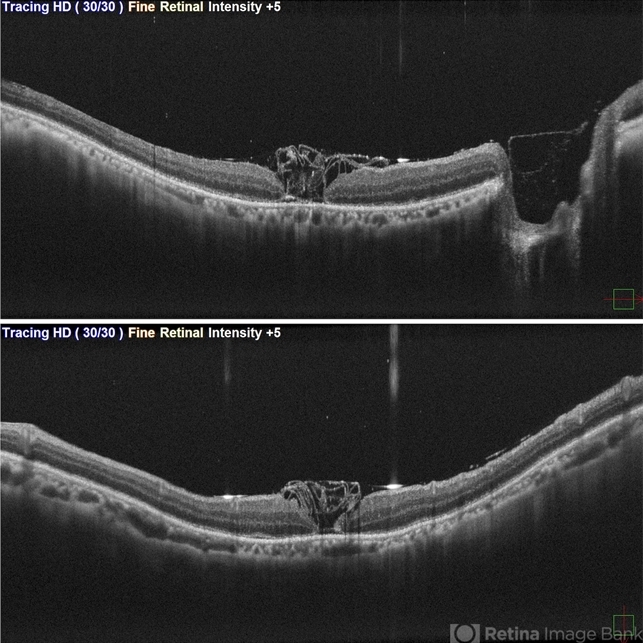

- FTMH, RD, Inverted ILM technique

- OCT showing stuffed ILM under oil on first post op day in a case of RRD with FTMH.